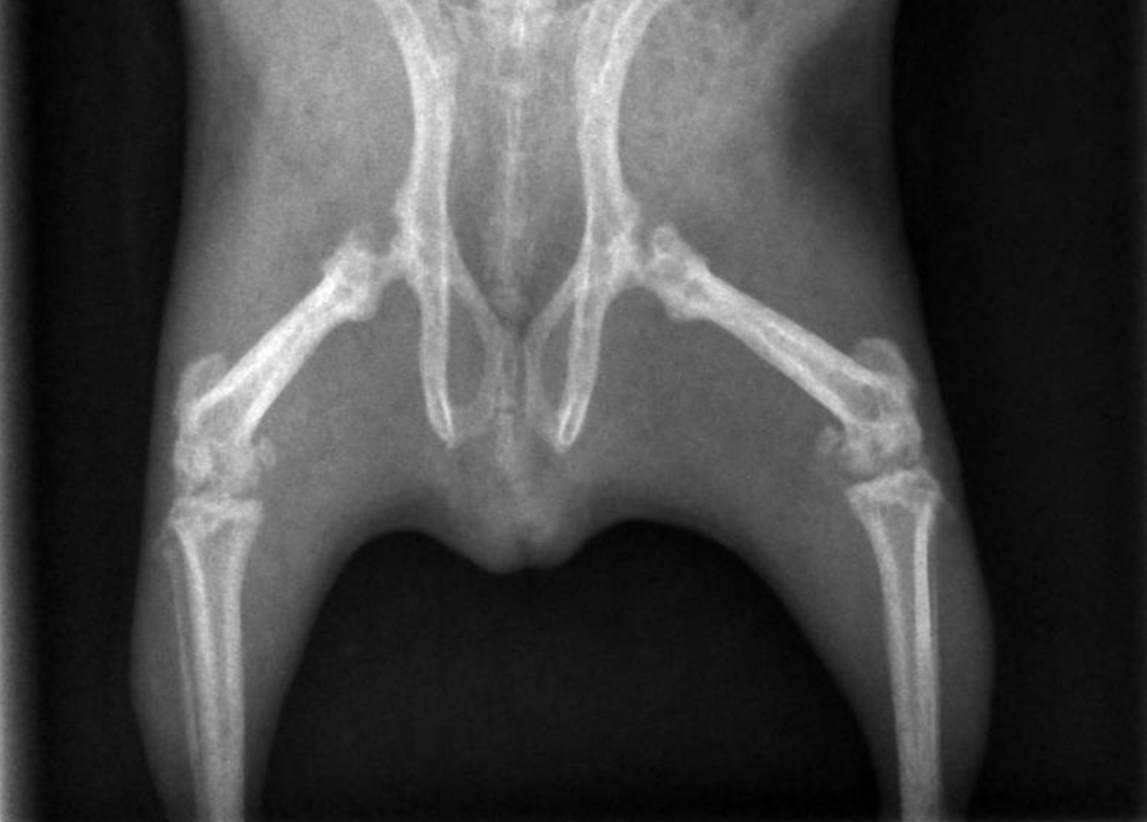

Ich habe sie dann schnell röntgen lassen, mit dem Ergebnis Osteodystrophie. Die Knochen waren schlecht mineralisiert, Wachstumsfugen teilweise nicht geschlossen, Arthrose in den Gelenken. Sie bekam Metacam, damit verschwand die Schonhaltung und sie wurde insgesamt munterer.

Bei Motte trat die OD vor allem in der Hüfte und den großen Hinterbeinknochen auf. Meerschweinchen, die Probleme im Kiefer(gelenk) haben, haben eine deutlich schlechtere Prognose. Platt gesagt, ein bisschen humpeln ist nicht so schlimm wie nicht kauen können.